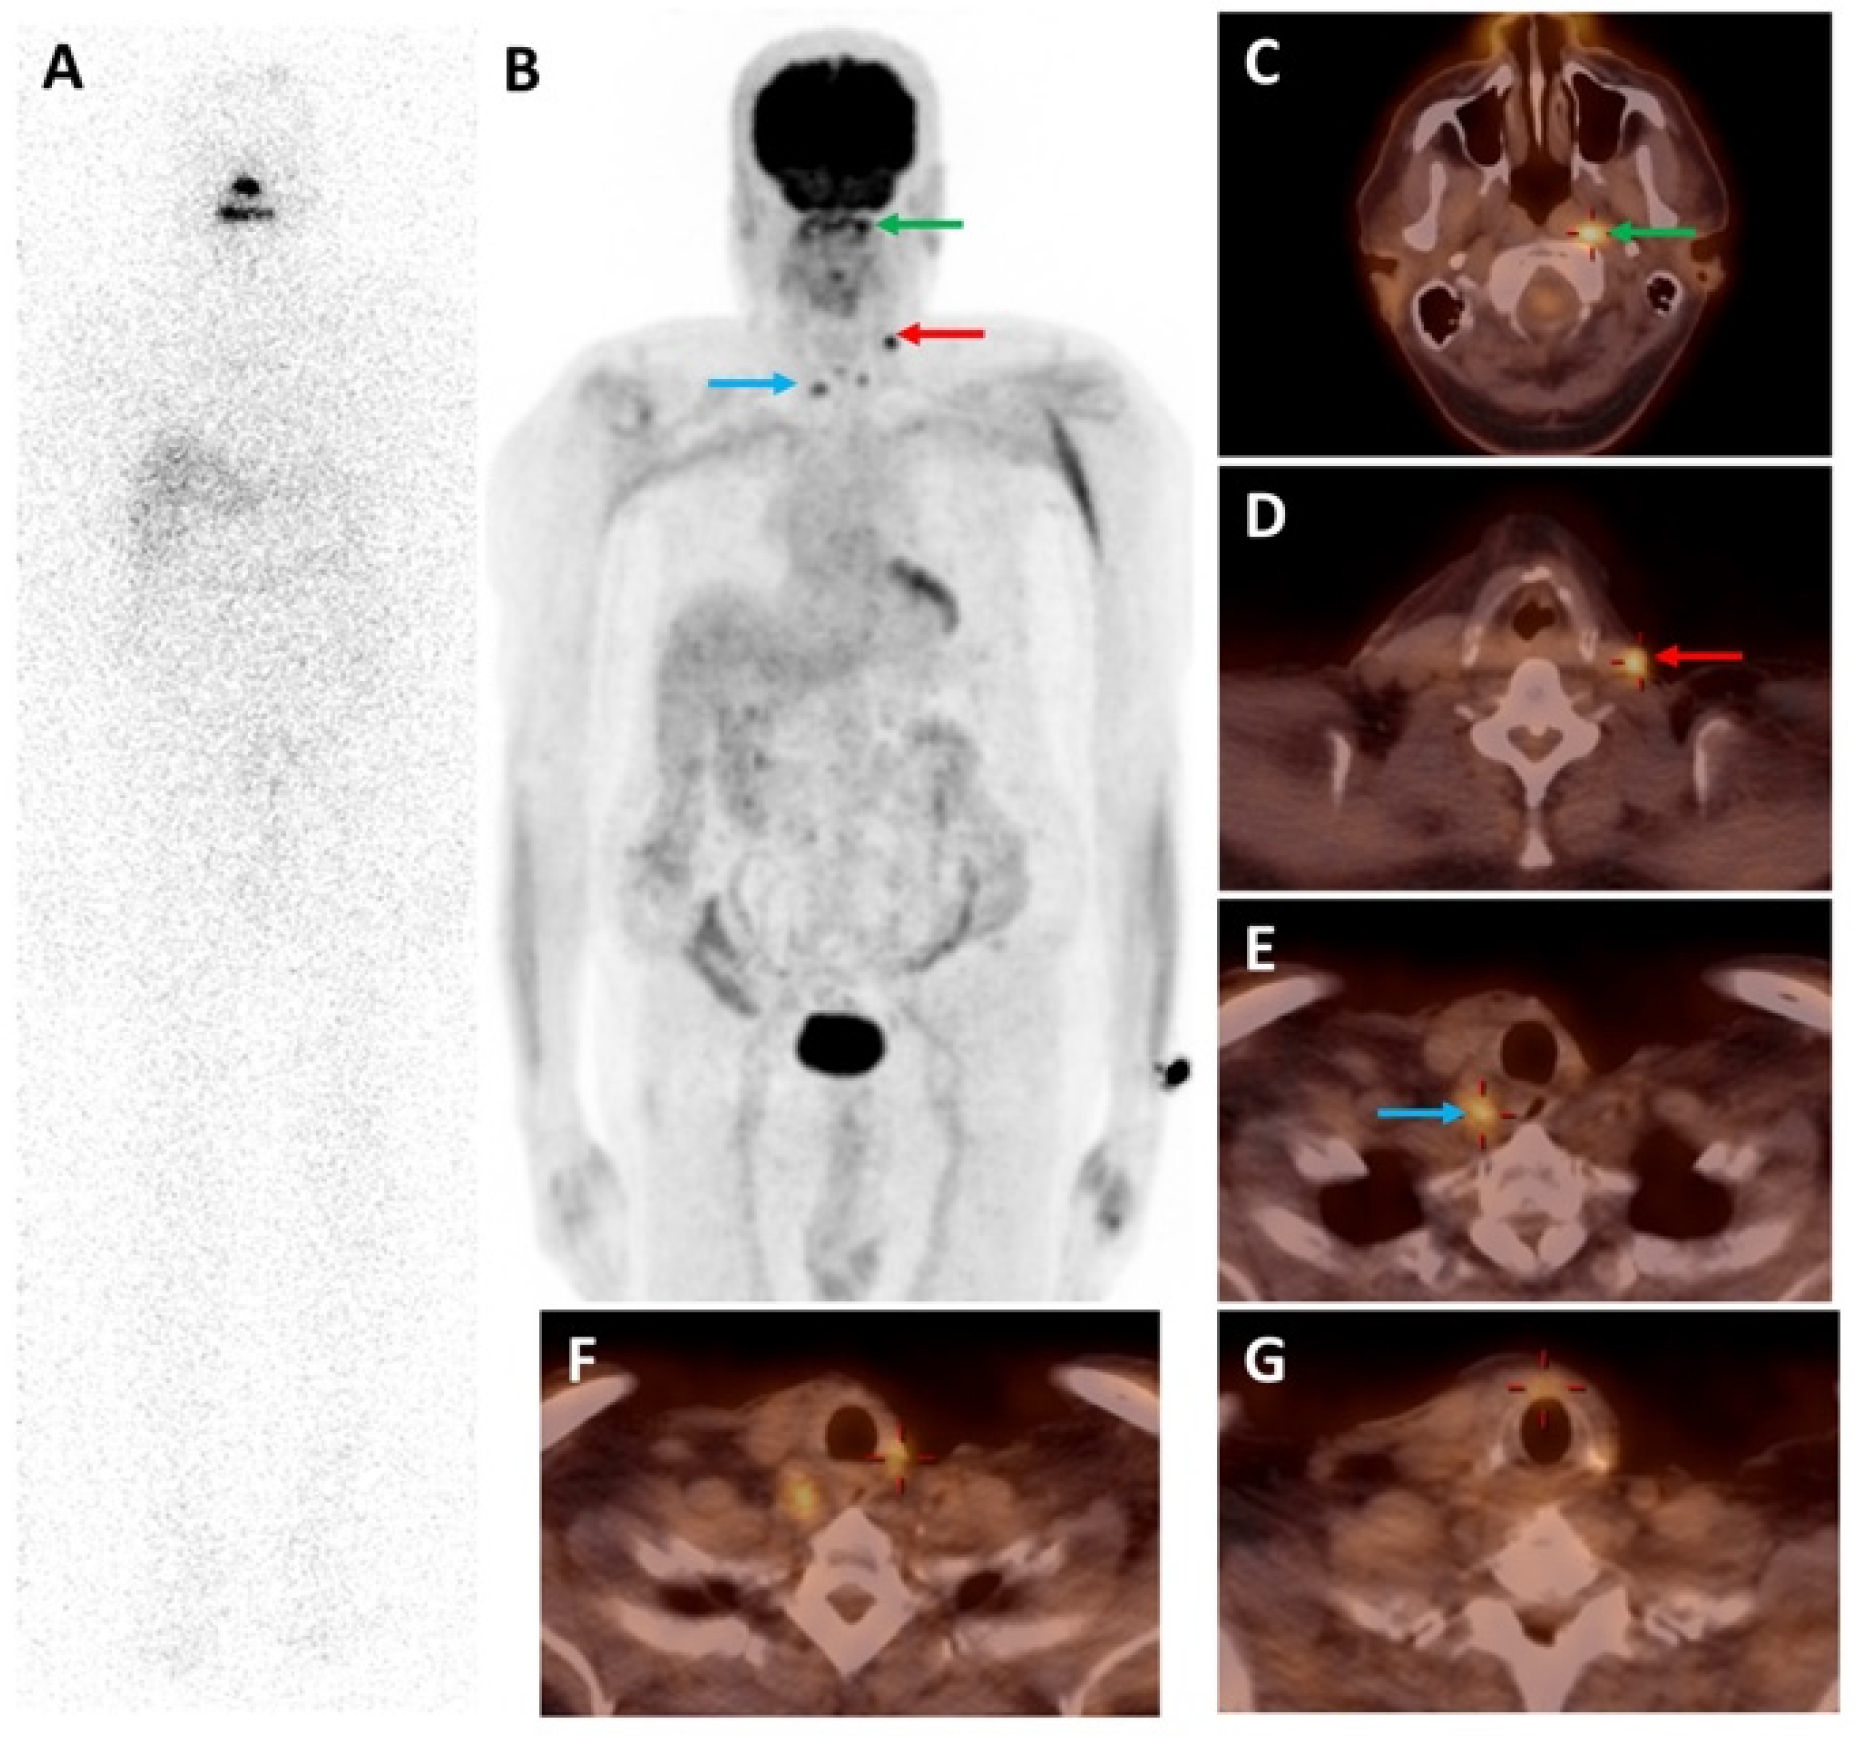

- Pitalua-Cortes, Q.; García-Perez, F.O.; Vargas-Ahumada, J.; Gonzalez-Rueda, S.; Gomez-Argumosa, E.; Ignacio-Alvarez, E.; Soldevilla-Gallardo, I.; Torres-Agredo, L. Head-to-Head Comparison of 68Ga-PSMA-11 and 131I in the Follow-Up of Well-Differentiated Metastatic Thyroid Cancer: A New Potential Theragnostic Agent. Front. Endocrinol. 2021, 12, 794759. [Google Scholar] [CrossRef] [PubMed]